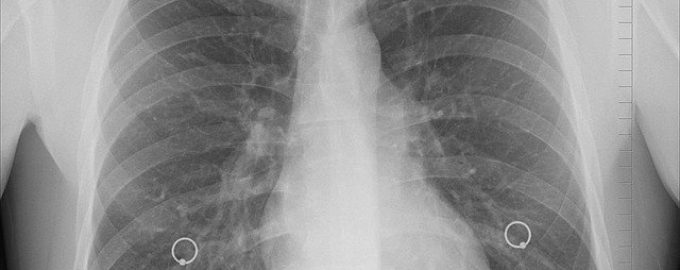

中共病毒 示意图。